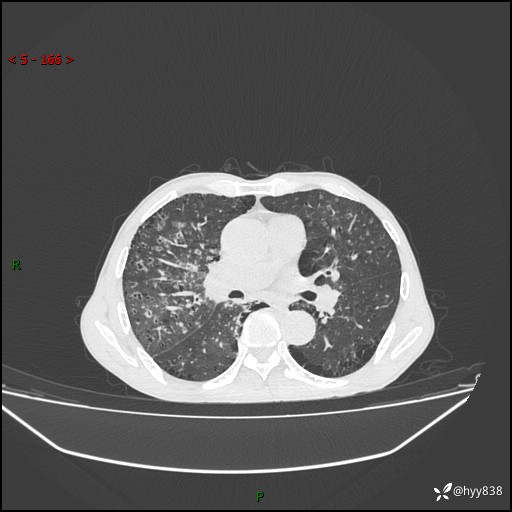

胸部CT平扫